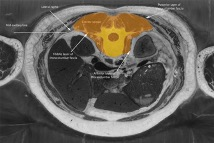

To emphasize the different volumes, cross-sections are shown below of (Figure 1) the vertebral column in yellow, and (Figure 2) the larger vertebral column region in amber color.